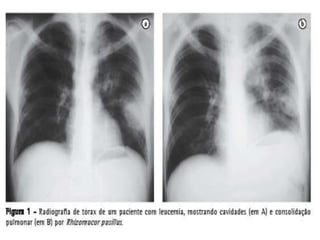

ZIGOMICOSES  Agente etiológico (Gênero):Phizopuss.p.Mucors.p.Absidias.p. As micoses produzidas por zigomicetos são denominados de zigomicoses ou mucormicoses.  As mucormicoses são geralmente graves. A infecção pode se localizar nos seios paranasais e cérebro, pulmões, aparelhos digestivos e em outros órgãos. A característica fundamental é a invasão dos vasos sanguíneos pelas hifas do fungo. A disseminação se faz através dos vasos sanguíneos, cartilagem nasal e nervos.  Amanda

ZIGOMICOSES  Transmissão – A infecção só ocorre em pacientes imunodeprimidos e não se conhece a transmissão de pessoa a pessoa, podendo ser por via aérea, digestiva (pães úmidos) ou mucocutânea.  Diagnóstico laboratorial – Secreções e tecidos. Exame direto (microscópico) – hifas largas e contínuas, não septadas com ramificações em ângulo reto.    Amanda

ZIGOMICOSES  Agente etiológico(Gênero):Phizopuss.p.Mucors.p.Absidias.p. As micoses produzidas por zigomicetos são denominados de zigomicoses ou mucormicoses.  As mucormicoses são geralmente graves. A infecção pode se localizar nos seios paranasais e cérebro, pulmões, aparelhos digestivos e em outros órgãos. A característica fundamental é a invasão dos vasos sanguíneos pelas hifas do fungo. A disseminação se faz através dos vasos sanguíneos, cartilagem nasal e nervos.  Amanda

ZIGOMICOSES  Transmissão –A infecção só ocorre em pacientes imunodeprimidos e não se conhece a transmissão de pessoa a pessoa, podendo ser por via aérea, digestiva (pães úmidos) ou mucocutânea.  Diagnóstico laboratorial – Secreções e tecidos. Exame direto (microscópico) – hifas largas e contínuas, não septadas com ramificações em ângulo reto.    Amanda